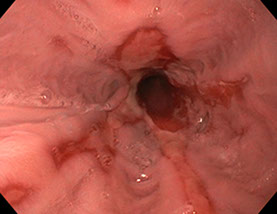

Estenosis Benigna del Aparato Digestivo

La estenosis benigna es un estrechamiento de un conducto, ya sea esófago, estómago o intestino. Esto ocasiona dificultad para pasar el alimento, con diferente sintomatología, como dificultad para tragar, vómitos, impactación de la comida, etc. Benigna significa que no es causada por cáncer.

La dilatación es un procedimiento que le permite a su médico dilatar, o ensanchar, un área estrechada de la vía digestiva. Los médicos pueden utilizar varias técnicas para este procedimiento.